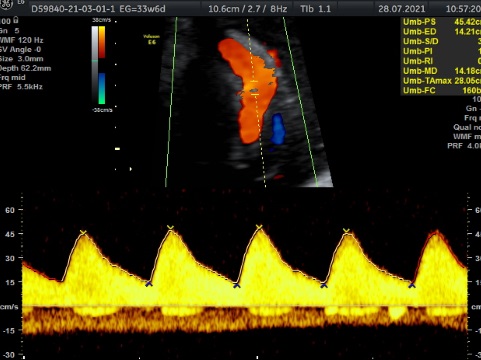

En cualquier semana de embarazo. Es un estudio que nos habla de la oxigenación que esta teniendo tu bebé a través de diferentes flujos sanguíneos ( cordón umbilical, cerebero, arterias uterinas, flujos del corazón. Es un estudio que se realiza para verificar Bienestar Fetal. Tiene una duración de 1 hora y al finalizar el estudio , se realiza 3D, 4D, 5D. Costo $1600